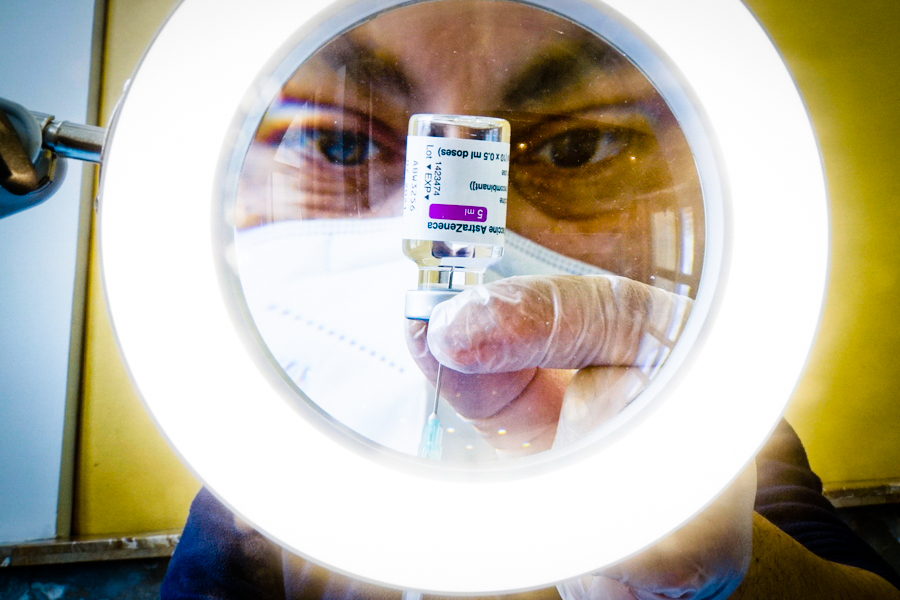

Προβληματισμένοι οι γιατροί για τους περιορισμούς στην επιλογή εμβολίου, στις γυναίκες 30-44 ετών

Προβληματισμό εγείρει στις γυναίκες αναπαραγωγικής ηλικίας το γεγονός ότι δεν μπορούν να επιλέξουν εμβόλιο, τη στιγμή που στο μοναδικό εμβόλιο στο οποίο έχουν πρόσβαση -αυτό της AstraZeneca– δεν έχουν ολοκληρωθεί οι μελέτες για την ασφαλή χορήγησή του στην εγκυμοσύνη. Την ίδια στιγμή, η Μεγάλη Βρετανία αποφάσισε να μην χορηγεί στις ηλικίες κάτω των 40 ετών […]

Βρετανία: Εναλλακτικό εμβόλιο αντί του AstraZeneca για τις ηλικίες κάτω των 40

Σημαντικές αποφάσεις σχετικά με το εμβόλιο της AstraZeneca παίρνει η Βρετανία, καθώς φαίνεται πως βρίσκεται προ των πυλών ο περιορισμός – ακόμη και η η διακοπή – της χορήγησης του σε ηλικίες κάτω των 40 ετών. Συγκεκριμένα, σύμφωνα με ρεπορτάζ των εφημερίδων Daily Telegraph και Independent, στη συγκεκριμένη ηλικιακή ομάδα θα προσφερθεί εναλλακτική λύση αντί του […]